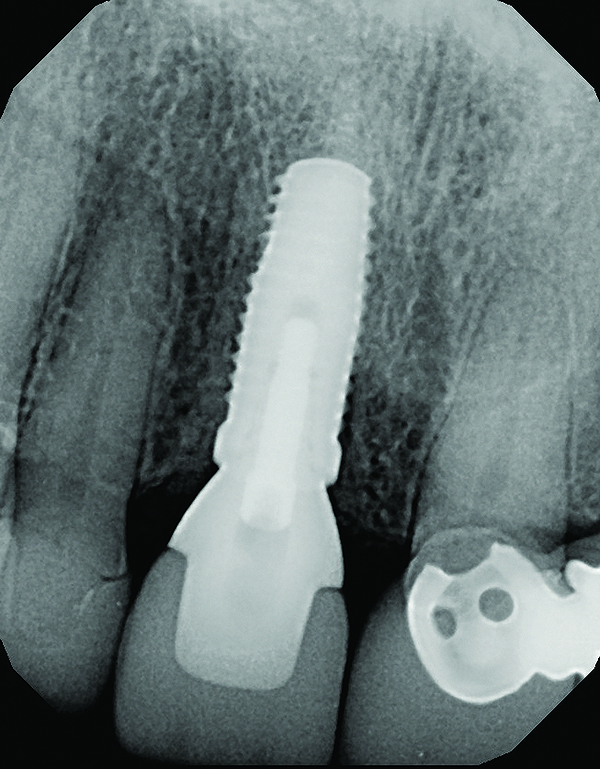

Fig 18. Radiograph taken immediately after placement of the definitive crown confirmed complete removal of all the cement.

Figure 18

The master cast and abutment were returned to the laboratory for fabrication of the restoration (Figure 15). An all-ceramic crown (e.max®, Ivoclar Vivadent) was fabricated on the custom abutment; it matched the contours of the adjacent central incisor. After completion of custom shading, the definitive abutment and crown were returned to the restorative dentist. The abutment was tried in (Figure 16), and a radiograph was taken to confirm complete seating between the abutment/implant and the crown/abutment. The definitive abutment screw was torqued to 20 Ncm, and the screw-access opening was blocked out with Teflon tape.

The crown was inserted and secured with a luting composite (Multilink® Automix, Ivoclar Vivadent) (Figure 17); a radiograph confirmed complete removal of excess cement (Figure 18). At the 4-month follow-up appointment, the soft tissues were healed within normal limits, and the patient was pleased with the esthetic outcome of the definitive restoration (Figure 19 and Figure 20).